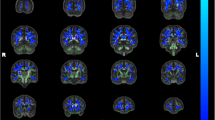

To visualize whole brain group differences, contrast maps compared voxel-wise ND and IF values for MCI versus HC and for AD versus HC (p < 0.01, FWE cluster corrected) (Fig. 2). Reduced white matter ND was observed bilaterally throughout the brain in AD and MCI compared to HC, although these differences had a more limited distribution in MCI. IF was increased in AD versus HC in the bilateral medial temporal lobe, whereas only one cluster in the left anterior medial temporal lobe showed increased IF in MCI versus HC. Voxel-wise differences in FA and MD are also shown in Fig. 2 for comparison. There were more extensive reductions in ND than in FA for both MCI and AD participants. There were more widespread increases in MD than IF for AD participants.

Whole-brain group differences in RSI and DTI metrics. Contrast maps show voxels with significantly lower ND or FA, and greater IF or MD, for MCI versus HC and for AD versus HC (p < 0.01, FWE cluster corrected). AD Alzheimer’s disease, FA fractional anisotropy, HC healthy controls, IF isotropic free water diffusion, MCI mild cognitive impairment, MD mean diffusivity